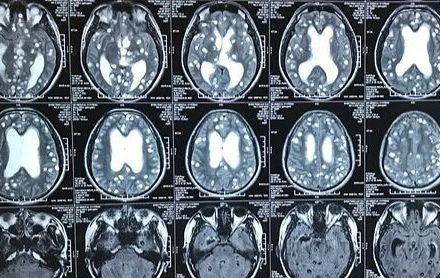

Với thói quen ăn gỏi cá, tiết canh, nem thính, thịt tái, người đàn ông phải nhập viện trong tình trạng đau đầu liên tục. Kết quả chẩn đoán bệnh nhân bị tổn thương não do ký sinh trùng (nang sán thần kinh Neurocysticercosis).